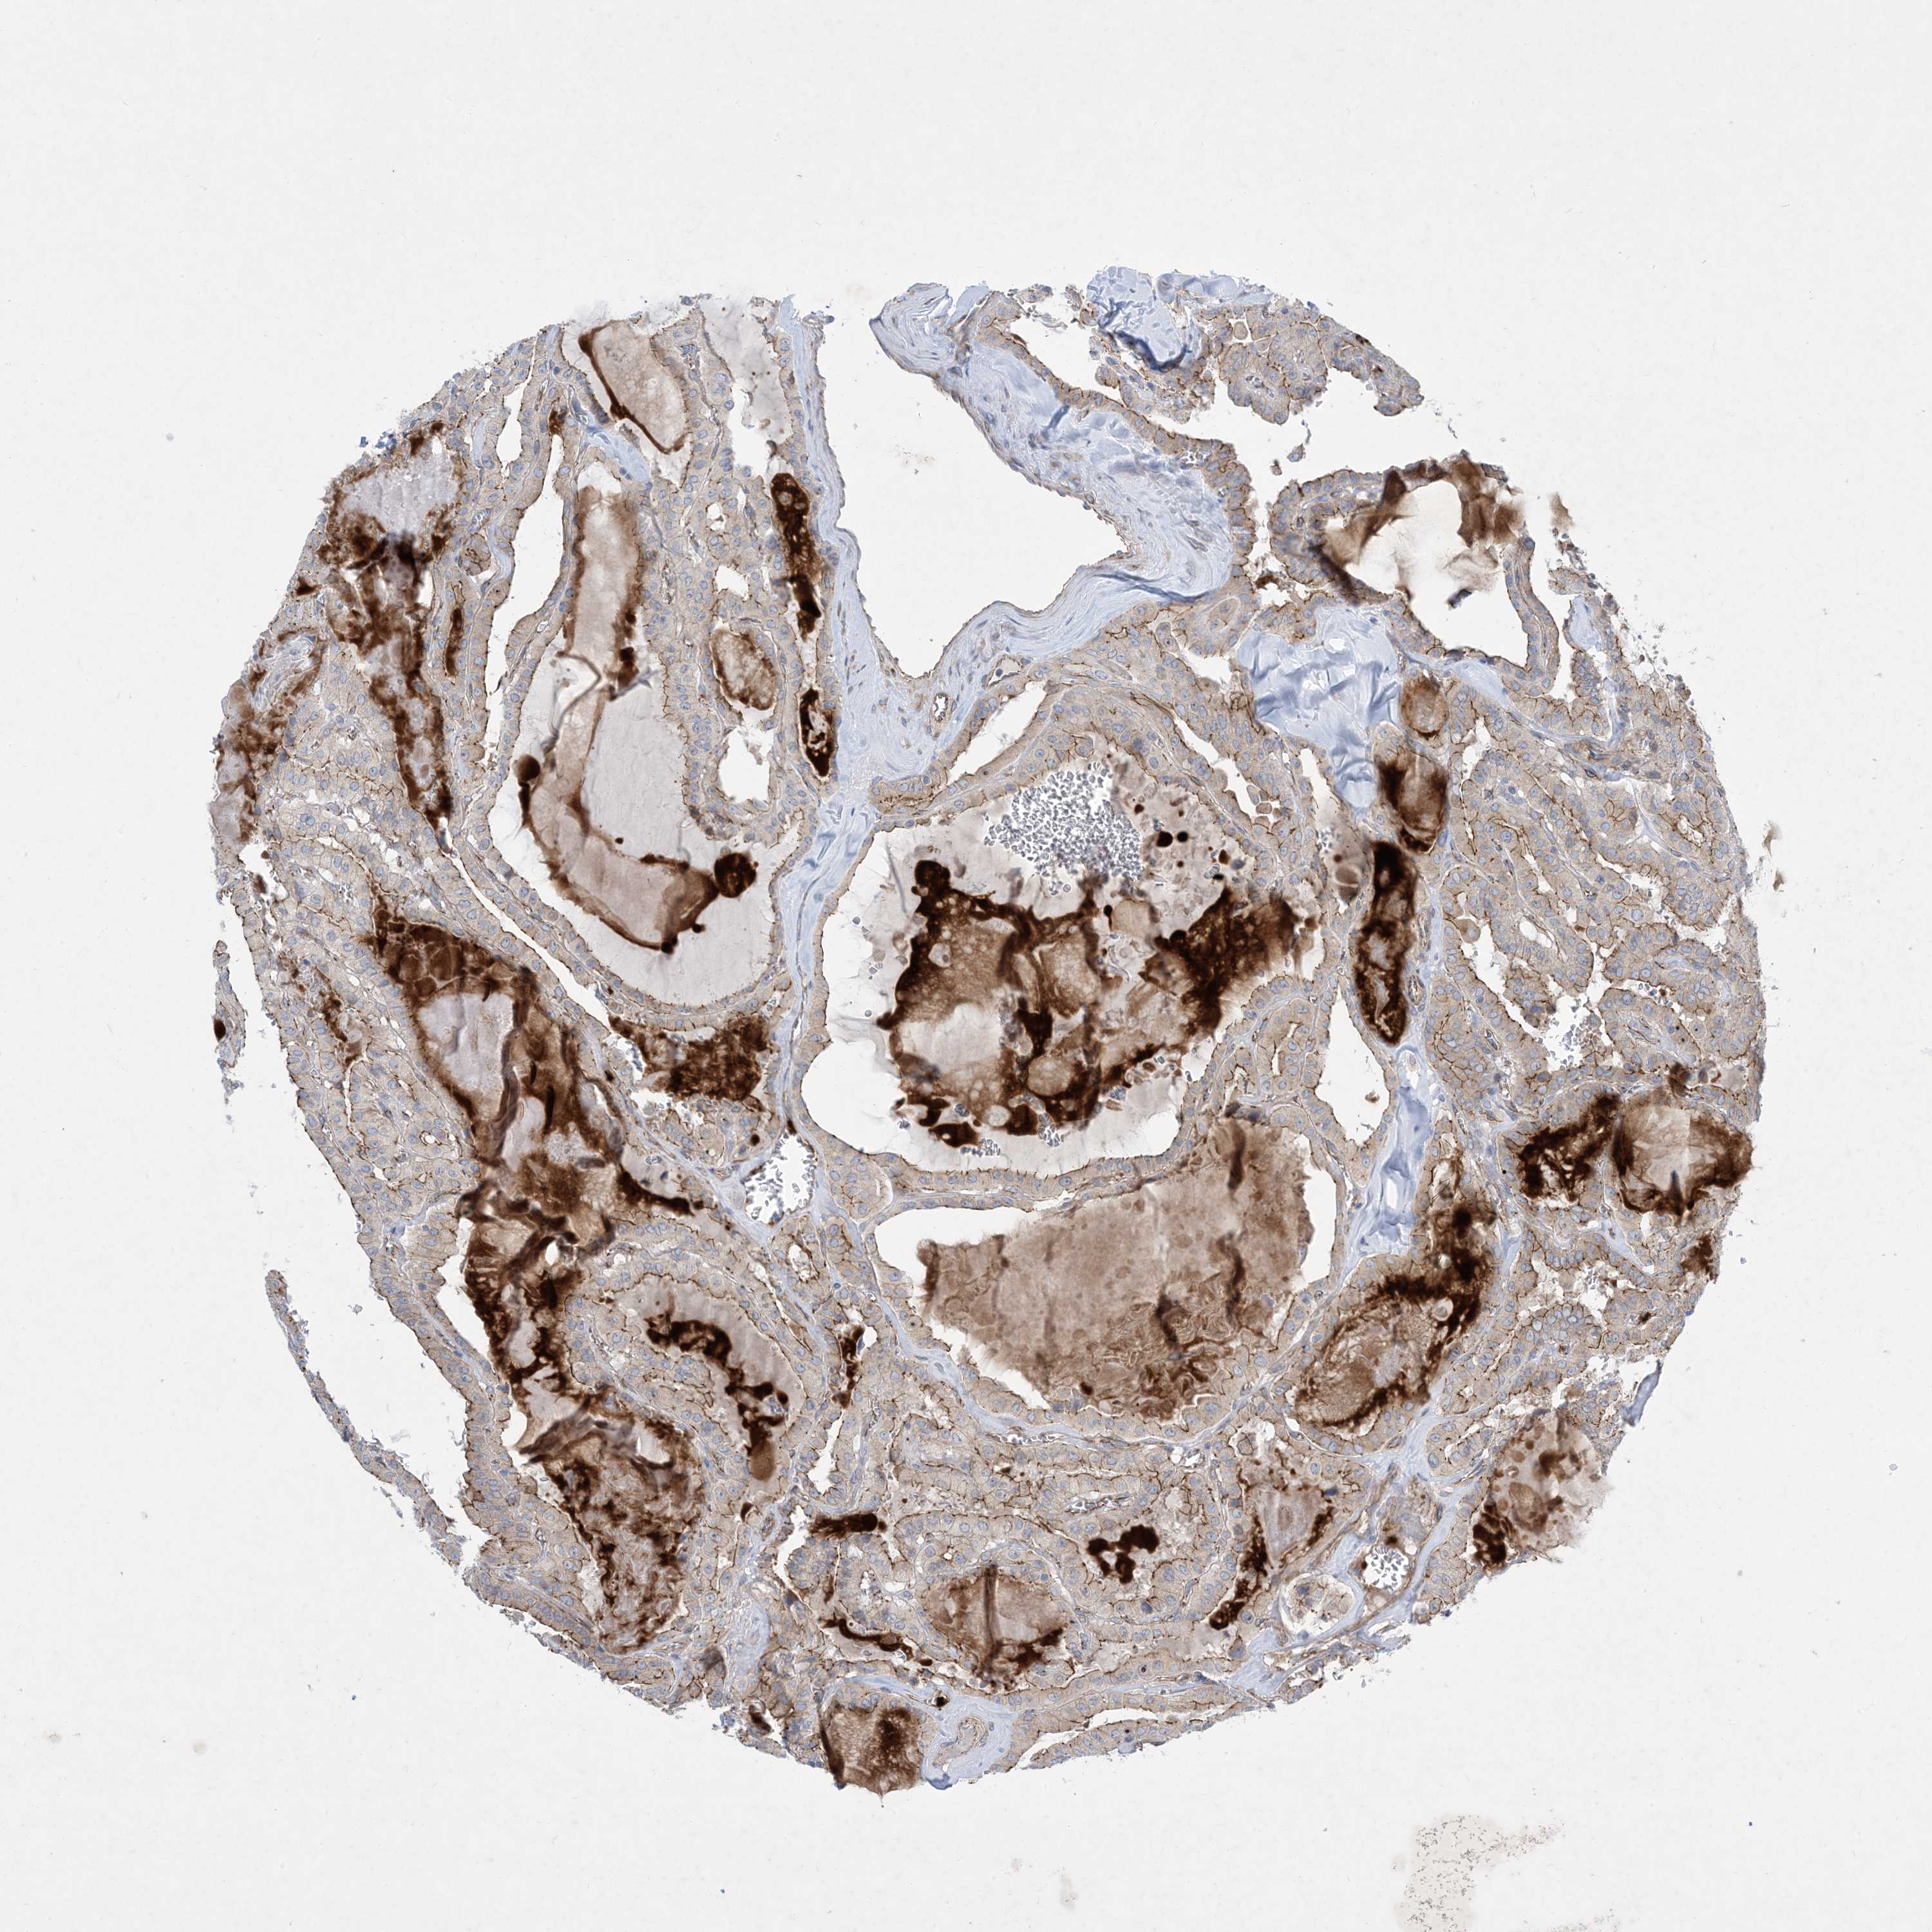

THYROID CANCER - Protein expressioni

A mouse-over function shows sample information and annotation data. Click on an image to view it in a full screen mode. Samples can be filtered based on level of antibody staining by selecting one or several of the following categories: high, medium, low and not detected. The assay and annotation is described here.

Note that samples used for immunohistochemistry by the Human Protein Atlas do not correspond to samples in the TCGA dataset.

Antibody stainingi

Antibody staining in the annotated cell types in the current human tissue is reported as not detected, low, medium, or high, based on conventional immunohistochemistry profiling in selected tissues. This score is based on the combination of the staining intensity and fraction of stained cells.

Each image is clickable and will lead to virtual microscopy that enables deeper exploration of all samples and also displays staining intensity scores, fraction scores and subcellular localization as well as patient and tissue information for each sample.

Antibody HPA035599

Staining

High

Medium

Low

Not detected

Intensity

Strong

Moderate

Weak

Negative

Quantity

>75%

75%-25%

<25%

None

Location

Nuclear

Cytoplasmic/membranous

Cytoplasmic/membranous,nuclear

Papillary adenocarcinoma, NOS

Follicular adenoma carcinoma, NOS